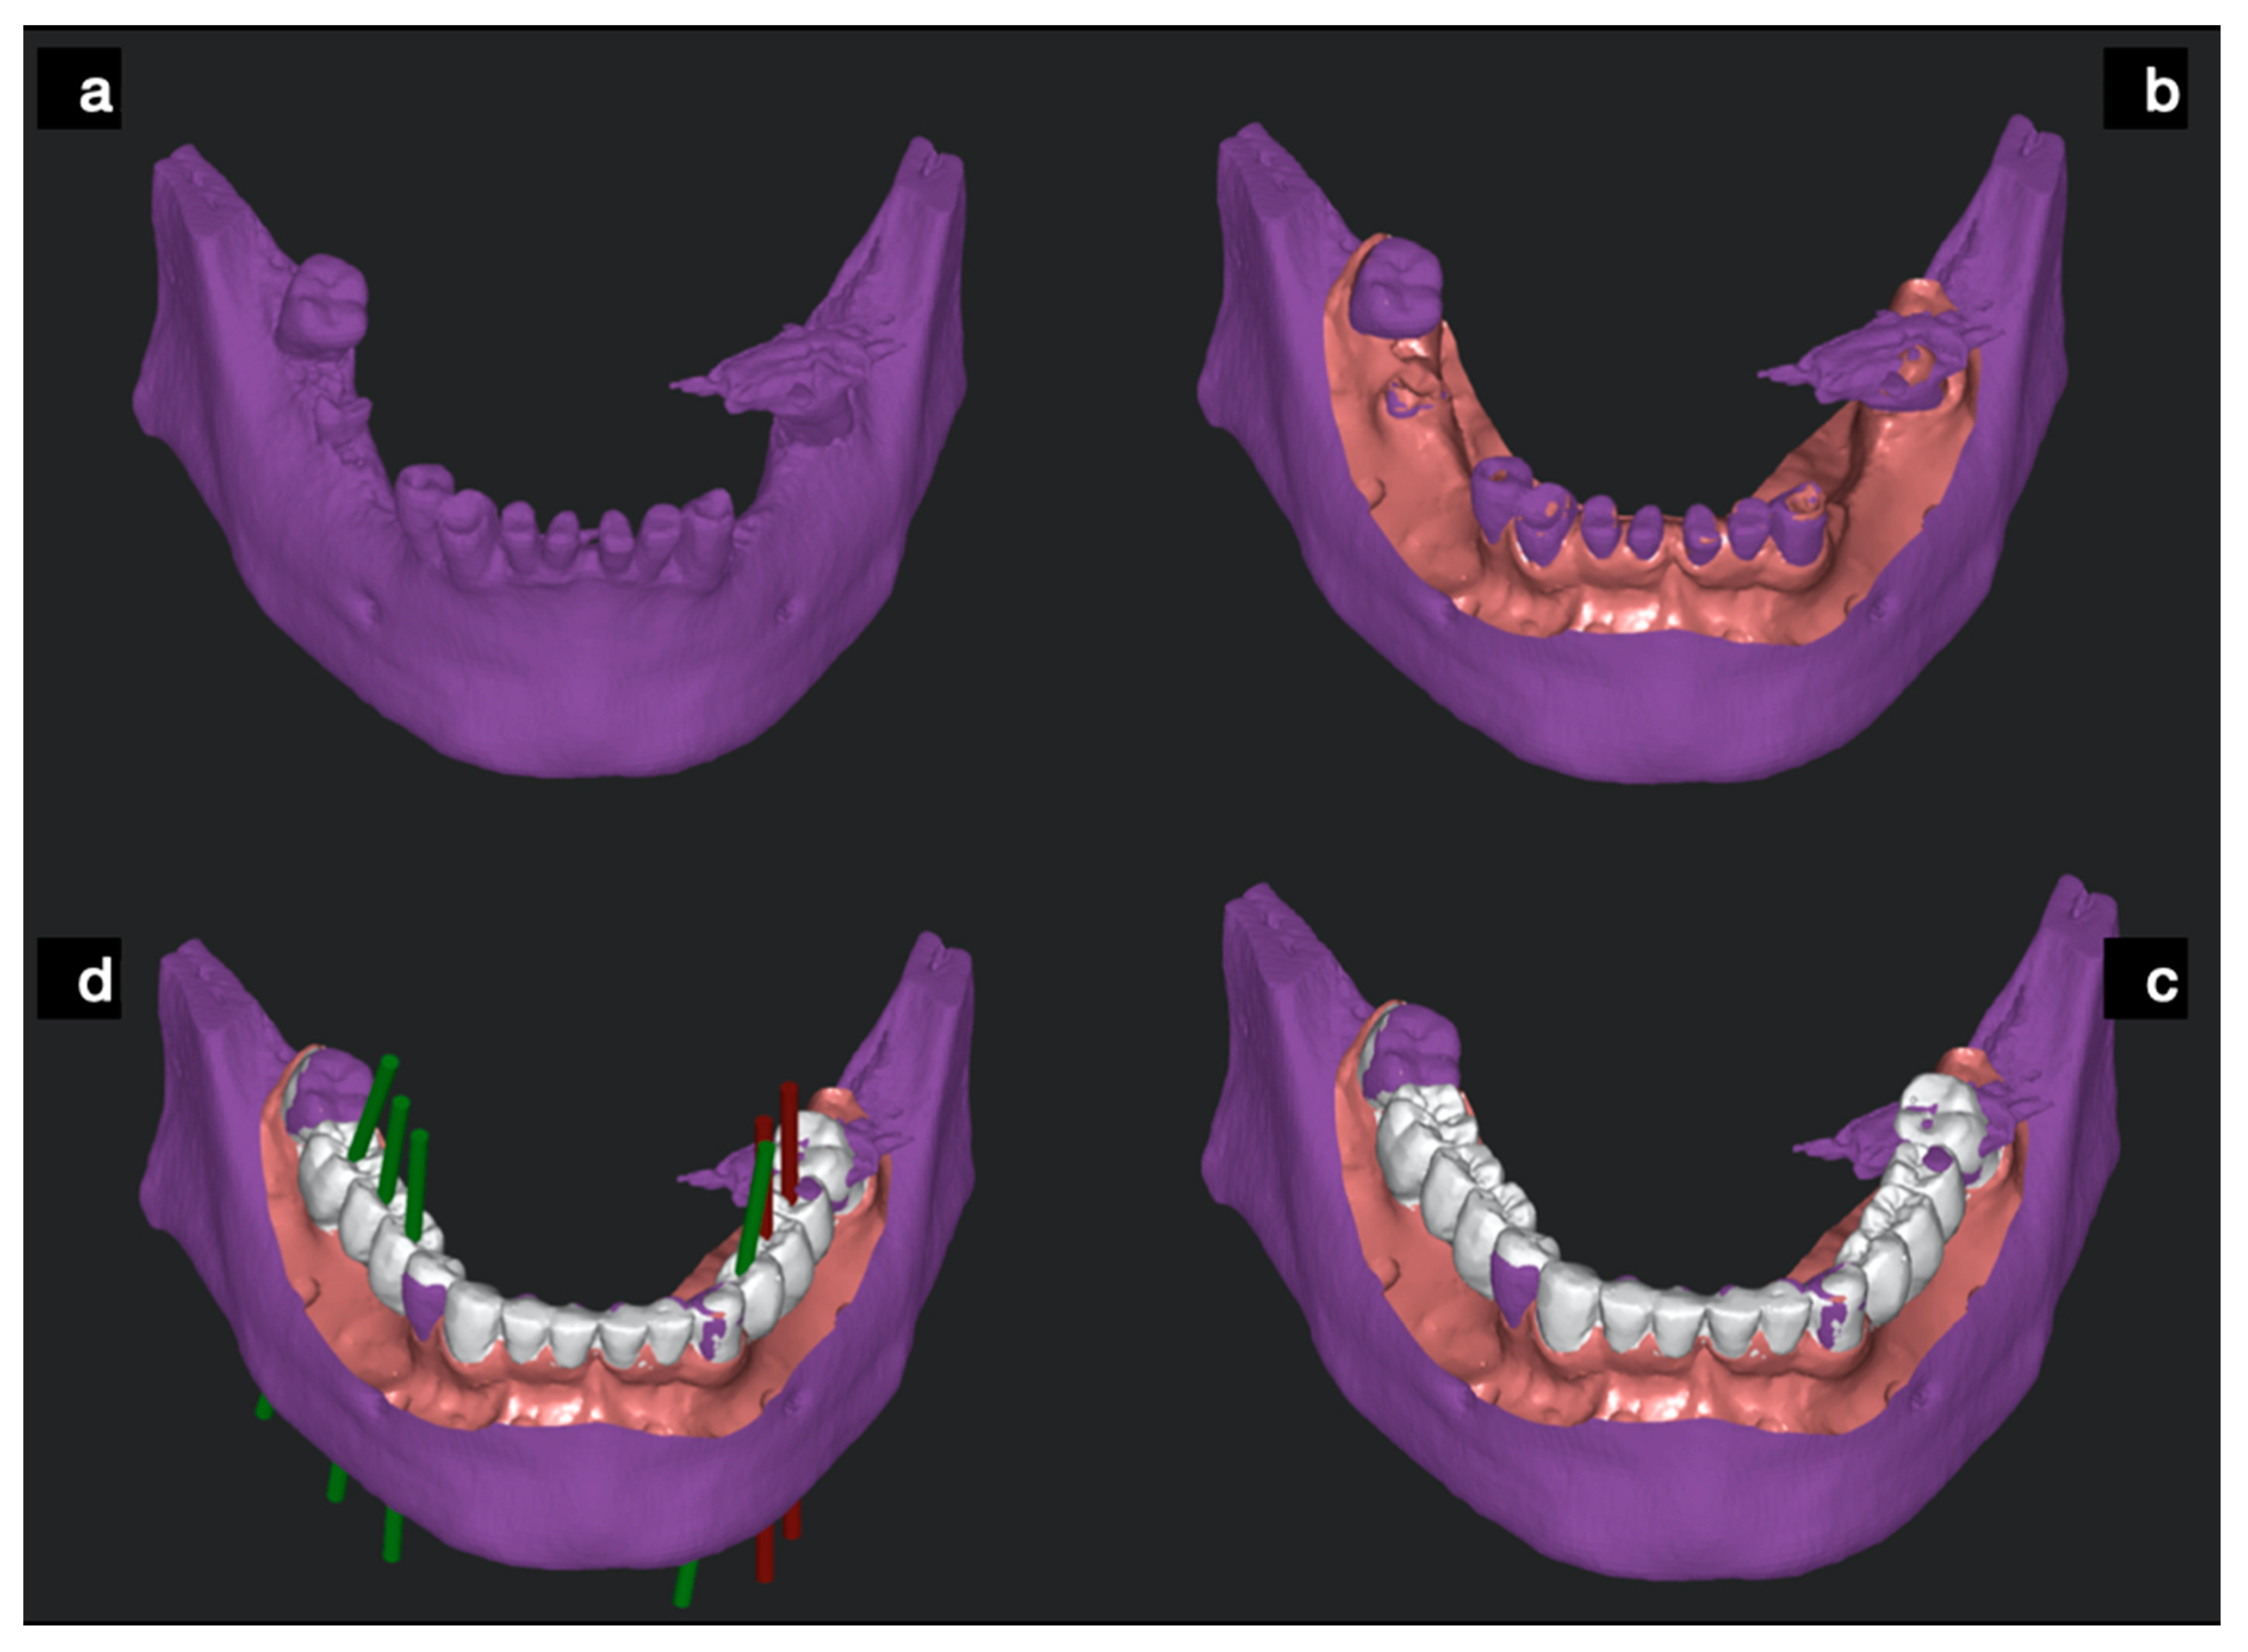

- A comparison between pre-op and post-op CBCT, based on radiographic volume superimposition;

- A comparison between post-op Standard Tessellation Language (STL) files obtained from an intra-oral scan (IOS) of the resin casts and the STL file obtained from the pre-op CBCT implant planning. In this case, the remaining teeth were used to align pre-op and post-op STL files to assess implants deviations.